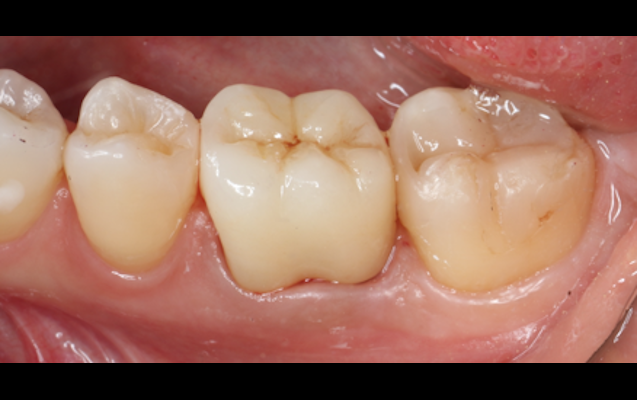

ダイレクトボンディングによる治療は、セラミックによる被せ物(クラウン)や詰め物(インレー)に比べて、歯を削る量を抑えることができる手法です。

当院では、色や透明感の異なる約十種類のプラスチックの中から、患者様の歯に合わせ選んだ多種類のプラスチックを重ね合わせていきます。従来の治療では困難であった自然な歯を再現可能としています。

(実際の症例)